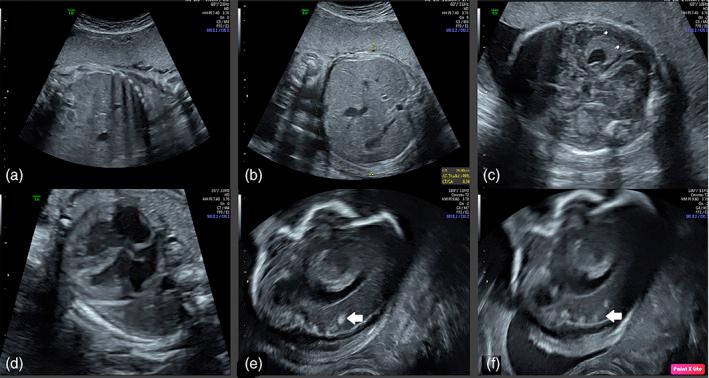

We present a case of congenital toxoplasmosis (TXP) in a woman with Toxoplasma gondii infection more than 6 months before conception. The woman has been treated with adalimumab for ankylosing spondylitis for 4 years until 5 months before conception. TXP serology at the first trimester was compatible with infection prior pregnancy. An ultrasound performed at 26 weeks gestation (WG) showed cerebral echogenic lesions compatible with intrauterine infection. Amniocentesis was performed which confirmed TXP fetal infection. Termination of the pregnancy was performed upon parent's requests and the fetal autopsy confirmed the diagnosis. Here, we discuss the potential role of immunosuppressive treatments, such as adalimumab, in the risk of congenital toxoplasmosis and the importance of counseling before pregnancy.

我们报告了一例先天性弓形虫病(TXP),该患者在受孕前 6 个月以上感染了刚地弓形虫。该患者因强直性脊柱炎已接受阿达木单抗治疗 4 年,直到受孕前 5 个月。孕早期的 TXP 血清学检查结果提示感染发生在妊娠前。妊娠 26 周时的超声检查显示符合宫内感染的脑回声病变。进行了羊膜穿刺术,结果证实胎儿感染了 TXP。根据父母的要求终止了妊娠,胎儿尸检结果也证实了这一诊断。在此,我们讨论了免疫抑制治疗(如阿达木单抗)在先天性弓形虫病风险中的潜在作用,以及妊娠前咨询的重要性。